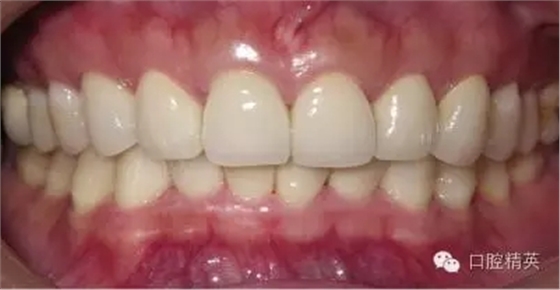

粘固后,對(duì)咬合關(guān)系進(jìn)行初步調(diào)整。三天后,復(fù)查,進(jìn)一步確認(rèn)咬合關(guān)系,必要時(shí)進(jìn)行調(diào)整(見圖12)。

LAVA 全瓷冠強(qiáng)度高,顏色自然,邊緣高度密合,切端可見半透明感,整體效果理想,與修復(fù)前(見圖1)相比取得了醫(yī)患均滿意的效果。